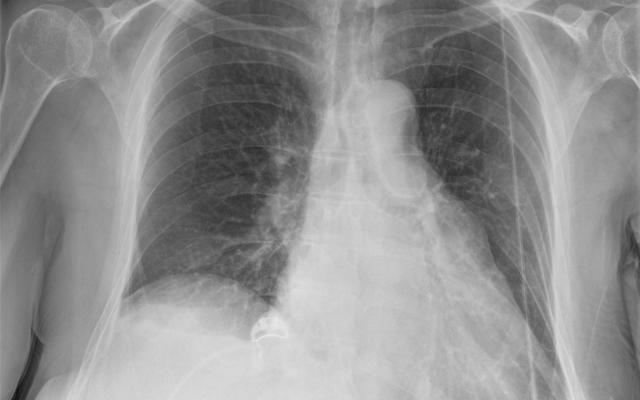

Een 74-jarige vrouw, bekend met astma en hartfalen, werd verwezen naar de Eerste Harthulp vanwege progressieve dyspneu sinds 3 weken. Deze dyspneu begon tijdens inspanning maar was inmiddels ook in rust en bij platliggen aanwezig. Het gewicht was onveranderd. Voorafgaand aan deze klachten had zij herpes zoster rechts op de thorax en in de nek ontwikkeld. Bij lichamelijk onderzoek zagen wij uitgebreide afwijkingen van de huid ter plaatse van dermatoom C4-C5 (figuur a), passend bij herpes zoster. Bij auscultatie hoorden we verminderd ademgeruis rechts basaal en licht expiratoir piepen. Oriënterend neurologisch onderzoek was niet afwijkend. Beweging van de arm…